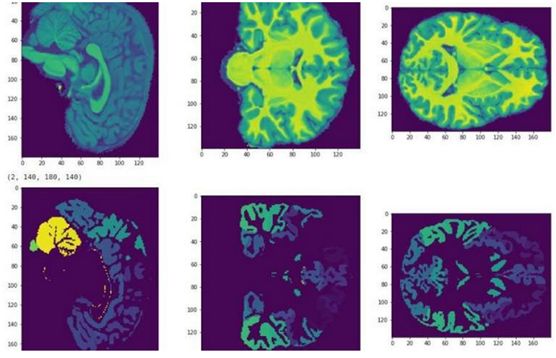

磁共振成像(MRI)是一项用来获取人体内部器官和组织图像的常用技术。科学家们想知道的是,我们是否可以从核磁共振脑图中预测出个体的智商水平。

Skoltech团队在参与竞赛的过程中,将神经网络应用于核磁共振图像的处理。

为此,他们建立了一个网络体系结构,这一网络结构可以使多个数学模型应用于同一数据,从而提高预测精确度,并且它们还采用了一种新的集成方法对MRI数据进行分析。